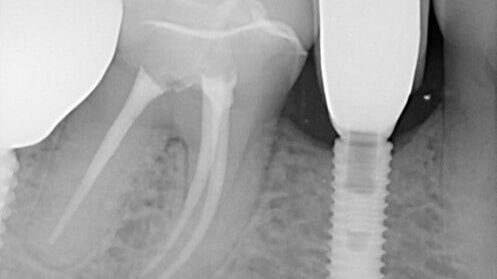

DIO Fractured Screw (#29i) – 0006

Dr. Mastrovich Presented on Broken Dental Implant Screw Removal at the Academy of Osseointegration, American Academy of Restorative Dentists and Dentsply PEERS Conference North America